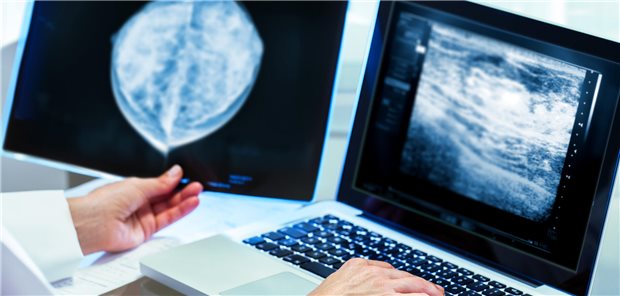

Symbolbild

© karelnoppe / stock.adobe.com

Beobachtungsstudie aus England legt nahe

In den ersten Jahren nach Atypie-Diagnose kein erhöhtes Brustkrebsrisiko